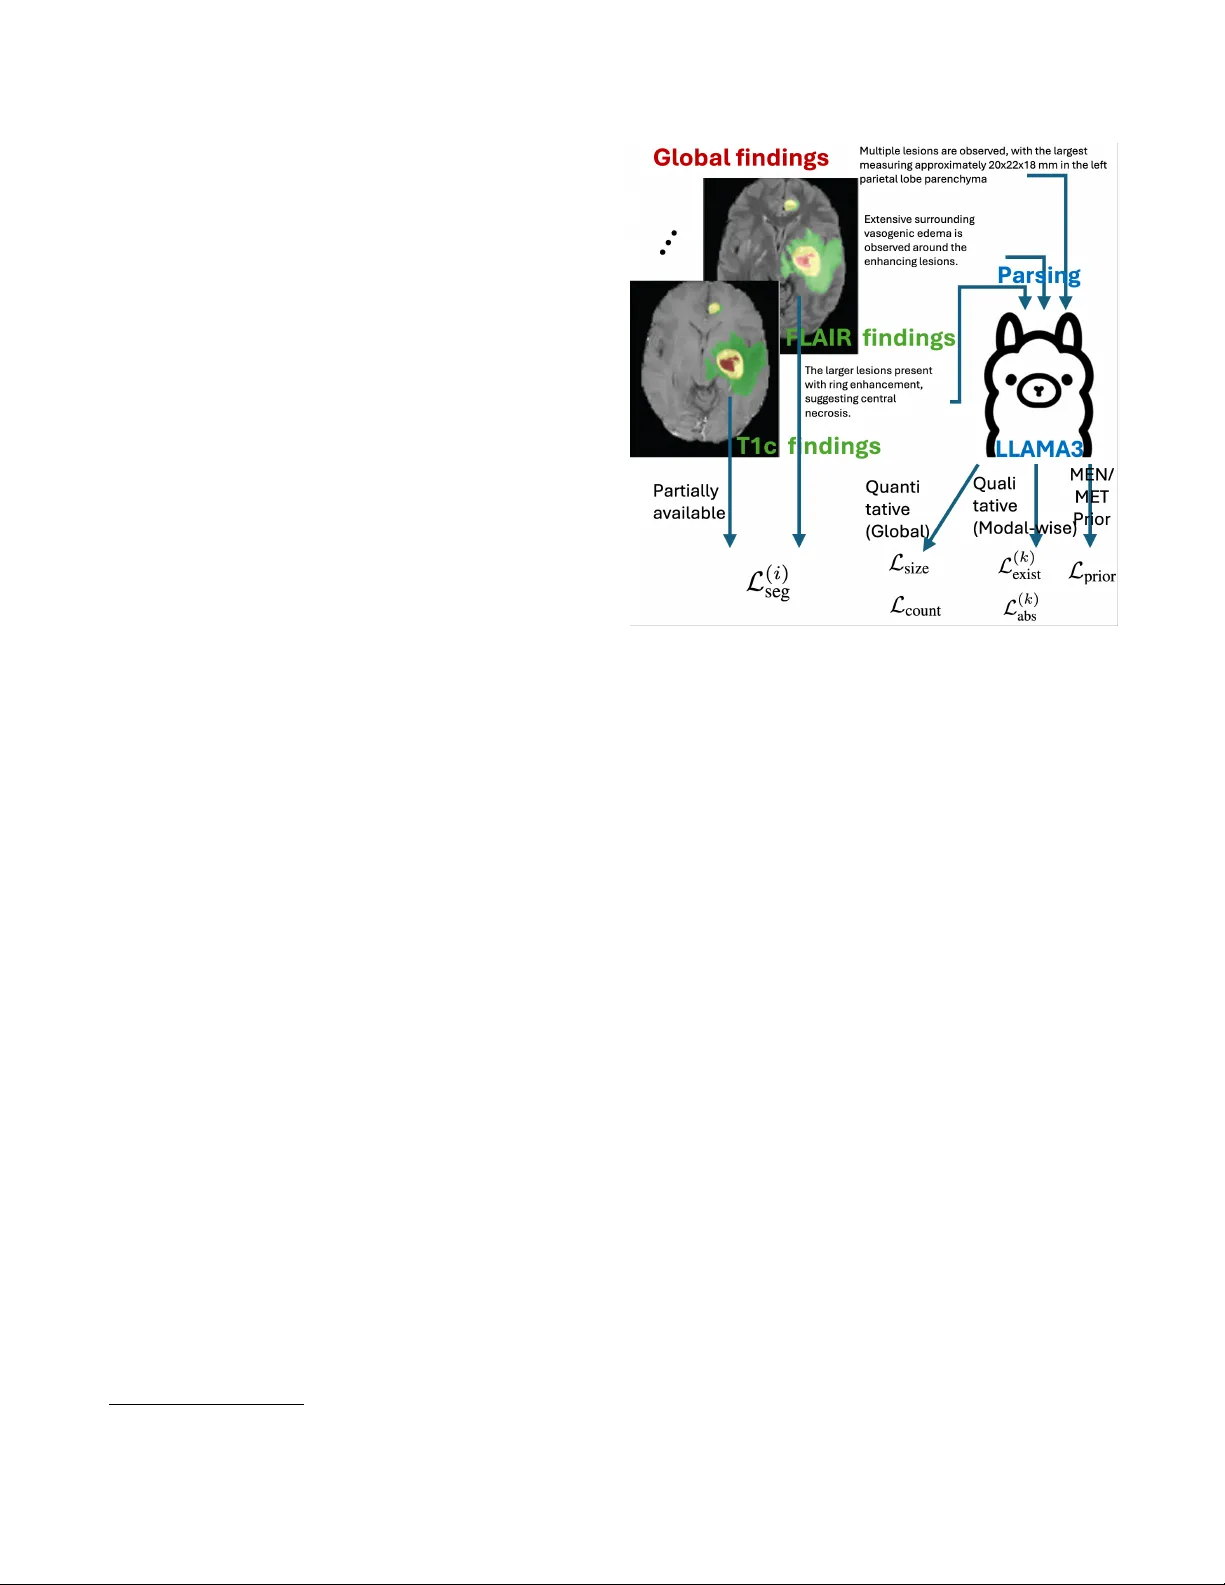

MUL TIMOD AL MRI REPOR T FINDINGS SUPER VISED BRAIN LESION SEGMENT A TION WITH SUBSTR UCTURES Y ubin Ge 1 † , Y ongsong Huang 2 , 3 † , Xiaofeng Liu 2 ∗ 1 Amazon A WS, 2 Y ale Uni versity , 3 T ohoku Univ ersity ABSTRA CT Report-supervised (RSuper) learning seeks to alleviate the need for dense tumor vox el labels with constraints deriv ed from radiology reports (e.g., volumes, counts, sizes, loca- tions). In MRI studies of brain tumors, ho wev er , we often in volv e multi-parametric scans and substructures. Here, fine- grained modality/parameter-wise reports are usually pro vided along with global findings and are correlated with different substructures. Moreov er , the reports often describe only the largest lesion and provide qualitativ e or uncertain cues (“mild, ” “possible”). Classical RSuper losses (e.g., sum volume consistency) can ov er-constrain or hallucinate unre- ported findings under such incompleteness, and are unable to utilize these hierarchical findings or exploit the priors of v ar- ied lesion types in a mer ged dataset. W e explicitly parse the global quantitati ve and modality-wise qualitati ve findings and introduce a unified, one-sided, uncertainty-aware formulation (MS-RSuper) that: (i) aligns modality-specific qualitativ e cues (e.g., T1c enhancement, FLAIR edema) with their cor- responding substructures using existence and absence losses; (ii) enforces one-sided lower -bounds for partial quantitative cues (e.g., largest lesion size, minimal multiplicity); and (iii) adds e xtra- vs. intra-axial anatomical priors to respect co- hort differences. Certainty tokens scale penalties; missing cues are do wn-weighted. On 1238 report-labeled BraTS- MET/MEN scans, our MS-RSuper largely outperforms both a sparsely-supervised baseline and a naiv e RSuper method. Index T erms — Report supervision, multimodal MRI, meningioma, brain metastases, segmentation. 1. INTRODUCTION Accurate delineation of lesion structures is a fundamental step in clinical diagnosis, intervention, and treatment planning [1]. Howe ver , vox el-wise annotation for 3D multimodal MRI is costly and subjectiv e, especially when substructures of tu- mor core (TC), enhancing tumor (ET), and edema (ED) must be delineated across sequences with different contrast mech- anisms [1]. How to utilize e xisting, routinely summarized radiology reports to aid (or assist) segmentation model train- † contribute equally . ∗ corresponding author: xiaofeng.liu@yale.edu ing is of great importance for more practical utilization of big medical data. T o exploit the v aluable and relatively large-scale text in- formation, early attempts usually form a multi-task learning with an auxiliary task in addition to the se gmentation with either the extracted tumor present/absent label for classifi- cation [2], or a contrastive language-image pre-training ob- jectiv e [3]. While the benefits of auxiliary tasks to segmen- tation are indirect and occasionally minor, the recently de- veloped Report-supervised learning (RSuper) [4] promises to directly le verage the detailed volumes, counts, and sizes e x- tracted from abundant abdominal CT radiology reports and enforces the corresponding loss functions alongside the con- ventional segmentation loss for only a small portion of seg- mentation labeled samples (e.g., 50 scans). This approach therefore largely reduces the b urden of manual labeling. Howe ver , in MRI studies of brain tumors, we often in- volv e multi-parametric scans of T1, T1c, T2, and FLAIR as well as substructures of TC, ET , and ED. In which the fine- grained modality/ parameter-wise finding reports are usually provided along with the global finding reports, and correlated to dif ferent substructures. Ho w to systematically exploit both the global descriptors (falx-/skull-base adjacency vs. deep parenchyma, approximate size, multiplicity , edema/midline shift) and modality-wise descriptors (T1c enhancement pat- tern; FLAIR hyperintensity) is largely undere xplored. Moreov er , the reports often describe only the largest le- sion, provide qualitativ e or uncertain cues (“mild, ” “possi- ble”). Specifically , in brain lesions, reports are often par- tially specified : many cases provide only the lar gest lesion size d max , omit axes for diameters, and/or use certainty quali- fiers ( mild , possible , equivocal ); and the counts are sometimes qualitativ e (“multiple”). Simply adopt the classical RSuper volume loss, which penalizes the difference of predicted and labeled sum volume of all tumors, may (a) learn to suppress small lesions that the report does not enumerate, or (b) unduly shrink tumors to match a partial volume hint. Finally , when combining image-report records from mul- tiple diseases, cohort-specific priors are lost. For e xample, BraTS-MET (metastases) typically includes multiple intra- axial parenchymal lesions, often with ring enhancement. In contrast, BraTS-MEN (meningioma) is typically e xtra-axial and dural-based (e.g., falx, skull base) with solid enhance- ment. A report-deri ved supervision should transfer across cohorts without imposing contradictory biases. A nai ve RSu- per loss cannot lev erage these strong anatomical priors. T o address these limitations, we propose a no vel multi- modality with substructure RSuper framew ork for brain le- sion segmentation. Our main contributions are: • Modality-Substructure Alignment: W e introduce a loss that links modality-specific report findings (e.g., T1c enhancement, FLAIR edema) directly to their corresponding segmentation substructures (ET and ED, respecti vely). • One-Sided Partial-Report Loss: W e propose a ”lo wer- bound” size loss and ”minimal-multiplicity” count loss to handle incomplete reports that only describe the largest le- sion or use qualitative counts, av oiding penalty for valid, unreported lesions. • Cohort-Specific Priors: W e integrate an anatomical prior loss that penalizes intra-axial predictions for MEN and extra-axial predictions for MET , guided by cohort-lev el cues from the reports. W e v alidated its ef fecti veness on the combined BraTS- MET and BraTS-MEN with segmentation and report 1 . 2. METHODOLOGY Our frame work trains a 3D se gmentation network using a par- tially segmented dataset, i.e., a lar ge set of image-report pairs ( D R ) and a small set of fully-masked data ( D M ). The model is trained with a composite loss. F or data in D M , we use a standard supervised segmentation loss, L seg (e.g., a combina- tion of Dice and Cross-Entropy loss). For data in D R , we introduce a nov el report-supervised loss, L report , designed to handle the hierarchical, qualitati ve, and partial nature of mul- timodal MRI reports. 2.1. Hierarchical Report Parsing and Mapping W e first employ a Large Language Model (LLM) with domain-specific prompts to parse each free-text radiology report. Critically , we categorize the extracted cues into two distinct types based on their nature and scope: (A) Quantitative Global Cues: These are specific measure- ments, typically found in the ”global findings” section, that apply to the entir e lesion or provide a total count. These are often partial (e.g., “largest lesion measuring 45x39x47 mm, ” ”multiple punctate... lesions”). (B) Qualitative Modality-Specific Cues: These are usually descriptiv e, non-numeric findings tied to a specific MRI sequence, which inherently map to tumor substructures. Though sometimes the tumor size is provided, it is the same as the global finding, which does not provide incremental information. For example, T1c often includes “obvious en- hancement, ” “ring enhancement, ” “no enhancement, ” while 1 ht tp s: // hu gg in g fa ce .c o/ da ta se ts/ Ji ay uL ei /R ad Ge nome- Brain_MRI/tree/main Fig. 1 . Overvie w of our proposed report-supervised frame- work. An LLM parses hierarchical findings from reports. Our losses align modality-specific findings, handle partial cues, and enforce anatomical location priors. FLAIR includes “surrounding extensiv e edema, ” “mild h y- perintense signal. ” Based on this parsing, we propose to establish a Modality- Substructure Alignment Principle . This is not a loss func- tion itself, b ut a crucial mapping rule that directs ho w con- straints are applied: • T1c findings (enhancement) constrain the Enhancing T umor ( P E T ) probability map. • FLAIR findings (edema, non-specific hyperintensity) constrain the Edema ( P E D ) probability map. • T1 or T2 findings (e.g., ”hypointense core”) constrain the T umor Core ( P T C ) map. • Global cues (e.g., total size, count) constrain the Whole T umor ( P W T ) map, where P W T = P E T + P E D + P T C . Uncertainty cues (e.g., ”possible, ” ”mild”) are parsed into a scaling weight λ ∈ [0 , 1] for the corresponding loss term. 2.2. Unified Report Constraint Loss ( L report ) Our primary report loss, L report , combines constraints from both qualitativ e and quantitative cues, applying them to the aligned substructure maps identified in § 2 . 1 . 2.2.1. Substructure Qualitative Existence and Absence Loss As identified, most modality-specific cues are qualitativ e (e.g., ”edema is present”) and lack quantitativ e volumes. W e cannot use a symmetric L1/L2 volume loss [4]. In- stead, we formulate a loss based on the existence or ab- sence of a finding. F or a gi ven substructure class k (e.g., k ∈ { ET , ED, TC } ), let V k be the predicted volume of P k ( x ) ≥ 0 . 5 for that substructure. If the report confirms the pr esence of substructure k (e.g., ”surrounding edema” → k = ED) with confidence λ k, pos , we apply an ”Existence Loss. ” This loss penalizes the model only if it fails to predict any presence (volume < 1 ) of that substructure L ( k ) exist = max(0 , 1 − V k ) , which encourages the model to segment at least 1 v oxel for class k , without halluci- nating a specific target v olume. Con versely , if the report explicitly confirms the absence of a substructure k (e.g., ”no enhancement” → k = ET), we apply an loss that penalizes any prediction for that class L ( k ) exist = V k . Therefore, we hav e L ( k ) exist =      max(0 , 1 − V k ) if presence confirmed, V k if absence confirmed, 0 otherwise. (1) 2.2.2. Global One-Sided P artial Cue Loss (Size and Count) W e handle the quantitati ve b ut partial nature of global cues: • Size Loss: Reports often provide only the 3D-dim or diameter(s) of the larg est lesion, d max . Let C pred be the set of predicted connected components for the whole tu- mor ( P W T ≥ 0 . 5 ). Let d c be the volume of a component c ∈ C pred . The loss is: L size = | d max − max c ∈ C pred d c | . This loss used mean absolute error , which is more robust to small inaccurate measure of d max . • Count Loss: Reports often use qualitativ e counts like ”multiple” or ”a fe w . ” W e parse this to a minimal inte ger N qual (e.g., ”multiple” → N qual = 2 ). W e apply a one-sided count loss: L count = max(0 , N qual − | C pred | ) . It penalizes the model if it predicts fewer than N qual lesions. Therefore, we hav e L global = w size L size + w count L count . 2.3. Cohort-Specific Anatomical Prior Loss ( L prior ) Finally , we lev erage global location cues (e.g., “falx, ” “parenchy- mal”) to identify the cohort (MEN or MET) and apply a strong anatomical prior . W e use pre-defined binary masks for the dura/extra-axial space ( M dural ) and the brain parenchyma/ intra-axial space ( M parench ). • If the report suggests Meningioma (MEN) , which is extra-axial, we penalize an y intra-axial predictions: L prior = X x ( P W T ( x ) · M parench ( x )) . • If the report suggests Metastases (MET) , which are intra-axial, we penalize extra-axial predictions: L prior = X x ( P W T ( x ) · M dural ( x )) . This loss ef fectiv ely guides the model to search in the correct anatomical compartment, resolving ambiguity and reducing false positi ves. 2.4. T otal Loss Function The model is first pre-trained on D M using L seg . It is then fine-tuned on the combined dataset D M ∪ D R . For a mixed batch B = B M ∪ B R , the total loss is: L total = 1 | B M | X i ∈ B M L ( i ) seg + w r | B R | X j ∈ B R L ( j ) report , where w r is a balancing weight for the report-based supervi- sion, and L report is the sum of our proposed constraint losses: L report = 3 X k L ( k ) exist + w size L size + w count L count + w prior L prior , where w size , w count , and w prior are weights for each component of the report-supervised loss. 3. EXPERIMENTS AND RESUL TS W e used two large-scale, multi-modal MRI segmentation datasets. Their associated radiology reports are manually generated in RadGenome-Brain MRI dataset [5] 1 . Each sub- ject has a global finding and four modality-wise findings. • BraTS-MEN (Meningioma): A collection of 1000 subjects (4000 3D mpMRI scans) with meningioma. Reports frequently describe extra-axial, dural-based lesions (e.g., ”falx cerebri, ” ”skull base, ” ”cerebellopontine angle”) with ”marked, ” ”uniform” enhancement on T1c. • BraTS-MET (Metastases): A collection of 238 sub- jects (952 3D mpMRI scans) with brain metastases. Reports describe ”multiple, ” ”parenchymal” (intra-axial) lesions, of- ten with ”ring enhancement” and ”extensi ve surrounding edema” on FLAIR. W e held out 50 MEN and 50 MET for testing, and re- maining subjects for training (all with reports, while 50 MEN and 50 MET has segmentation masks). The LLM parser was implemented using Llama 3.1 70B as in [4] with prompts engineered to e xtract the hierarchical attributes, uncertainty weights, and cohort priors. W e used the 3D nnU-Net framework as our base segmen- tation architecture due to its strong performance. The model was pre-trained on BraTS2018 for Glioblastoma (dif ferent tu- mor from MEN or MET) with the supervised CE loss for labeled substructures of TC, ET , and ED [1]. No report is T able 1 . Dice Score on the held-out test sets. Method T est Set WT (DSC) TC (DSC) ET (DSC) Masks-Only MEN 0.481 0.323 0.370 R-Super [4] MEN 0.452 0.301 0.353 MS-RSuper(Ours) MEN 0.554 0.428 0.489 Masks-Only MET 0.420 0.385 0.321 RSuper [4] MET 0.443 0.391 0.333 MS-RSuper(Ours) MET 0.529 0.494 0.452 av ailable. Loss weights were set empirically as w r = 0 . 2 , w size = 1 . 0 , w count = 0 . 5 , and w prior = 0 . 2 . W e compare three methods: (1) Masks-Only (Base- line): fine-tuned only on the 100 labeled scans ( D M ). (2) R-Super [4] finetuned on D M ∪ D R , using the summed volume and count applied to the ”Whole T umor” (WT = ET+ED+TC) prediction. (3) Ours MS-RSuper: multimodal with substructure supervised by L report . As shown in T able 1, our method largely outperforms both baselines. The Masks-Only model suf fers from poor general- ization, as expected from only 50 labels in each disease. The RSuper [4] baseline dose not provides improv ement, since its symmetric “summed volume” loss is confused by the par- tial reports (e.g., only the largest lesion), leading to subopti- mal performance. Our MS-RSuper achiev es the highest Dice scores across all substructures and both cohorts. The gains are promising in the MET dataset, where our L count (handling “multiple” lesions) and our qualitative losses ( L exist ) (which align ’edema’ to P E D and ‘enhancement’ to P E T ) are critical. For the MEN dataset, L prior (enforcing extra-axial location) was ke y to reducing false positi ves in the brain parenchyma. An ablation study (T able 2) on the MET dataset confirms that each of our proposed loss components contributes to the final performance. The quantitativ e, partial-cue losses ( L exist ) provide the first major boost by handling size and count. Adding the qualitati ve modality-aligned losses ( L global ) fur- ther improves performance by correctly using the T1c and FLAIR cues. Finally , the cohort prior ( L prior ) provides an additional gain by penalizing anatomically implausible pre- dictions. 4. CONCLUSION W e introduced a novel report-supervised learning framework tailored for the complexities of multi-parametric brain MRI and substructure segmentation. Unlike prior work on CT , our method addresses three ke y challenges: (1) it aligns qualita- tiv e modality-specific findings with their corresponding seg- mentation substructures using novel existence and absence losses, (2) it uses one-sided, uncertainty-aware losses to ro- bustly handle partial quantitative reports (e.g., “largest lesion only , ” “multiple”), and (3) it integrates cohort-lev el anatom- ical priors (intra- vs. extra-axial) deri ved from report key- words. W e ev aluate on a large dataset of 1238 meningioma and metastases scans, our approach largely outperformed both T able 2 . Ablation study on the BraTS-MET T est set (WT Dice). Each component of our proposed loss ( L exist , L global , L prior ) provides a cumulati ve benefit. Method WT (DSC) Masks-Only (Baseline) 0.420 + L exist (Partial size/count) 0.475 + L exist + L global (Adds qualitativ e) 0.513 + L exist + L global + L prior (Full MS-RSuper) 0.529 a sparsely-supervised baseline and a nai ve application of ex- isting RSuper methods. This work demonstrates that by de- signing losses that faithfully reflect the hierarchical and often- incomplete nature of radiology reports, we can ef fectiv ely lev erage large-scale text data to improve multi-class segmen- tation in multimodal imaging. 5. COMPLIANCE WITH ETHICAL ST AND ARDS This retrospectiv e study used open-access human subject data; no additional ethical approv al was required. 6. A CKNO WLEDGMENTS Supported in part by NIH R21EB034911 and NVIDIA Aca- demic Grant Program. 7. REFERENCES [1] Xiaofeng Liu, Helen A Shih, Fangxu Xing, Emiliano Santarnecchi, Georges El F akhri, and Jonghye W oo, “In- cremental learning for heterogeneous structure segmenta- tion in brain tumor mri, ” in MICCAI . Springer , 2023. [2] Y ongtao Zhang, Haimei Li, Jie Du, Jing Qin, Tianfu W ang, Y ue Chen, Bing Liu, W enwen Gao, Guolin Ma, and Baiying Lei, “3d multi-attention guided multi-task learning network for automatic gastric tumor segmenta- tion and lymph node classification, ” IEEE TMI , 2021. [3] Louis Blankemeier , Joseph Paul Cohen, Ashwin Ku- mar , Dave V an V een, Syed Jamal Safdar Gardezi, Mag- dalini P aschali, Zhihong Chen, Jean-Benoit Delbrouck, Eduardo Reis, Cesar T ruyts, et al., “Merlin: A vision lan- guage foundation model for 3d computed tomography , ” Resear ch Squar e , pp. rs–3, 2024. [4] Pedro RAS Bassi, W enxuan Li, Jieneng Chen, Zheren Zhu, Tian yu Lin, Sergio Decherchi, Andrea Cav alli, Kang W ang, Y ang Y ang, Alan L Y uille, et al., “Learn- ing segmentation from radiology reports, ” in MICCAI . Springer , 2025. [5] Jiayu Lei, Xiaoman Zhang, Chaoyi W u, Lisong Dai, Y a Zhang, Y anyong Zhang, Y anfeng W ang, W eidi Xie, and Y uehua Li, “ Autorg-brain: Grounded report genera- tion for brain mri, ” , 2024.